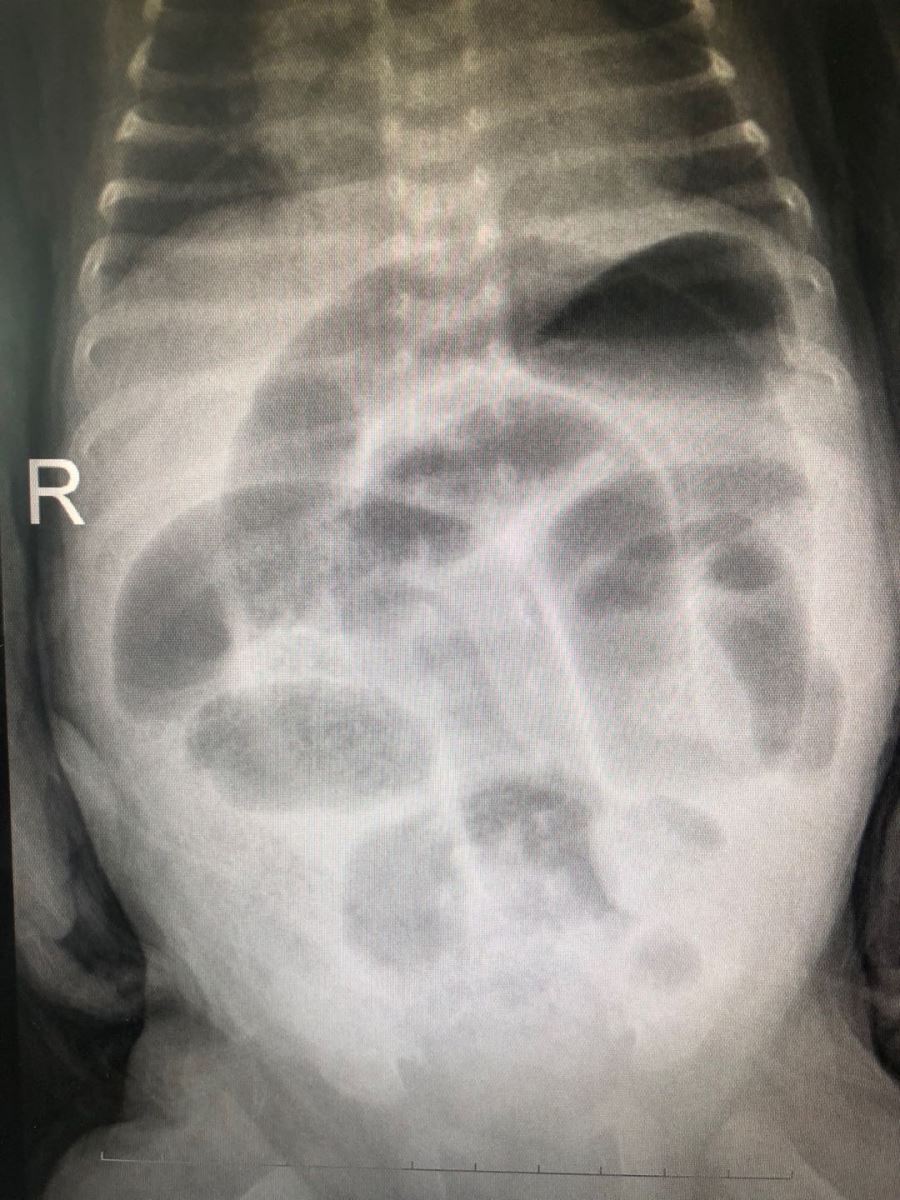

患儿男性,出生28天,体重3300g。主因腹胀2天,频繁呕吐1天收入我院儿科诊疗中心。经查体:患儿腹部膨隆,左侧阴囊肿大,皮肤发红,阴囊内可触及囊性包块。右侧阴囊未触及异常。入院后完善相关检查及化验,腹部平片显示:肠梗阻。彩超检查显示:左侧腹股沟疝,疝内容物为肠管。由小儿外科急诊会诊后,考虑该患儿诊断为1.左侧腹股沟嵌顿性疝;2.病理性黄疸。患儿左侧腹股沟区包块无法还纳,不排除外肠坏死,有急诊手术指征,无手术禁忌。急转至小儿外科,手术由小儿外科负责人宋希春主刀,佟鑫医生协助,在全麻下行左侧腹股沟疝内容物还纳、疝囊高位结扎术。术中探查疝内容物为小肠,肠管色泽呈暗黑色,无活力,探查至正常肠管后,解除嵌顿用温盐水湿敷嵌顿肠管半小时,肠管颜色无明显改变。术中诊断为1.左侧嵌顿性腹股沟疝;2.肠坏死。决定行肠切除吻合术。腹股沟切口吻合困难,另行开腹探查切口,肠管扩张明显,坏死肠管距回盲部约20cm,切除坏死肠管,行回肠端吻合,小肠减压。术后患儿恢复良好,于术后第一天排气、排便,术后7天顺利出院。

患儿男性,早产2个月,出生1个月零22天,体重3000g。主因腹胀、哭闹1天,伴发热来我院就诊。经查体:患儿腹部膨隆,下腹压痛,叩诊呈鼓音,右侧腹股沟区隆起,阴囊肿大约3.0*2.0cm,可触及包块,用手不能还纳入腹腔,阴囊透光试验呈阴性。左侧阴囊肿大,较软,平卧位后不能变小,阴囊透光试验呈阳性。入院后完善相关检查及化验,急查彩超:考虑疝,嵌顿疝待排外,左侧睾丸鞘膜积液,腹部肠管胀气。腹部拍片显示:肠梗阻。故急转至小儿外科,考虑该患儿被诊断为:1右侧嵌顿性腹股沟疝;2.左侧睾丸鞘膜积液。排除相关手术禁忌症后,手术由小儿外科负责人宋希春主刀,纪额尔敦医生协助,在全麻下行右侧嵌顿性腹股沟疝疝内容物还纳、疝囊高位结扎术。术者见肠管暗紫色,解除嵌顿后肠管暗红色,无坏死,同时发现右侧睾丸暗紫色,与家属沟通后保留睾丸。术后患儿恢复良好,已排气、排便。术后复查彩超,睾丸血运良好。